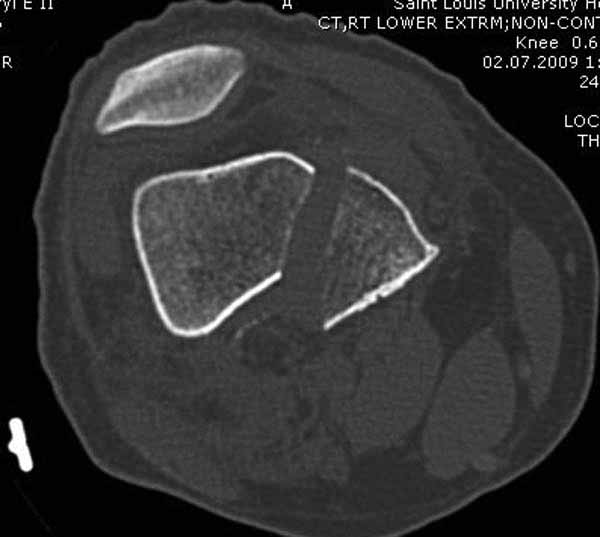

И не обратите, коллега, пока не сделаете четкие анфасные снимки (лучше с дистракцией) где будет четко визуализироваться малоберцовая кость. Думается, что и КТ здесь будет уместно, дабы не пропустить возможное флексионное повреждение (перелом Hoffa).

А теперь по поводу лечения перелома. Среди всех чрез/меж-мыщелковых переломов в 38% сопровождются переломом в корональной плоскости, т.е перелом Hoffa. Nork et al, J Orthop Trauma, 87:564, 2005.

Однако в случае, представленном Константином Никитиным, не может быть применён ни ретроградный ни антеградный остеосинтез. Причина - нереально выполнить вышеуказанные необходимые требования, касающиеся дистальных блокирующих винтов. Из-за низкого перелома латерального мыщелка (перелом Hoffa) невозможно через него провести хотя бы 2 блокирующих винта, поскольку линия перелома мыщелка расположена либо на уровне верхушки межмыщелковой ямки либо незначительно проксимальнее. Поэтому авторам, с моей точки зрения, необходимо прислушаться к рекомендациям Джолдаса.